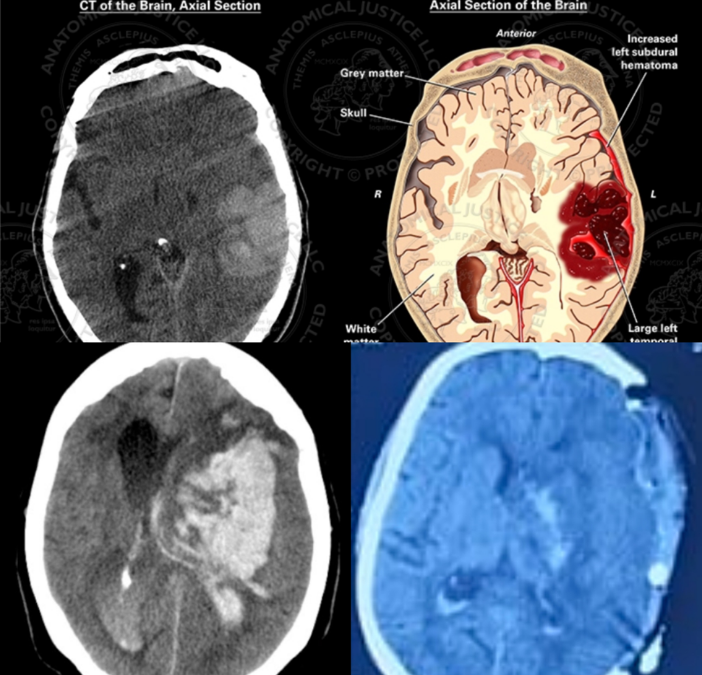

Understanding Intracranial Hematoma (ICH) and the Role of Surgery: Insights from a Neurosurgeon in Thane

What is Intracranial Hematoma (ICH)? An intracranial hematoma (ICH) occurs when blood vessels within the brain rupture, leading to the accumulation of blood in the skull. This condition can cause significant pressure on the brain, leading to...